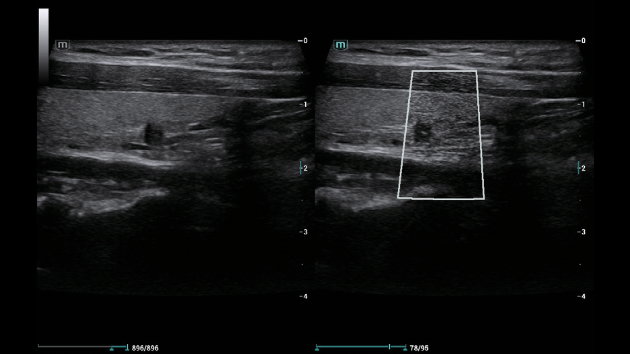

ZST+ ??? ???? ?? ???

ZST+ ???? ???? ??? ???? ??? ?????. ??? ???? ?? ? ???? ?? ??? ?? ??? ?????. ??? ??? ? ?? ??? ??? ???? ?????? ??? ???? ???? ??? ?? ?? ?? ?? ???? ?? ??? ?? ??? ?????.